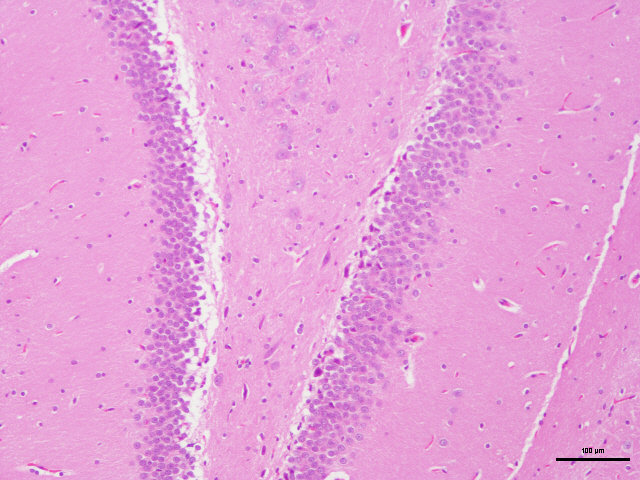

病理学的所有切片,都必须通过一种以上的染料,通过各种不同的方法,将切片中各种不同的物质,在不 同染液的作用下,将其显示出来,使之在光学显微镜下,能够完全的观看各种结构。例如,HE染色,好质 量的切片可以清晰地显示出许多不同的结构,细胞核着蓝黑色,细胞浆着粉红色,软骨着蓝色等。清晰的 结构为诊断提供可靠的依据,因此,染色技术也是病理技术中的重要组成部分,必须不断地总结,方能提 高。如果染色不好,切片染色一团糟,红蓝不分,结构不清,层次不明,影响了镜下的观察,直接影响了 临床诊断,染色结果的好坏直接关系到诊断的准确性。

:细胞核被染成深蓝黑色;细胞浆被染成粉红色;软骨及钙盐被染成蓝色;胶原 纤维染成淡粉红色,嗜酸性细胞及嗜酸性颗粒呈鲜红色;弹力纤维呈淡粉红色;某些蛋白性物呈粉红色 等。

样片参考:

脑